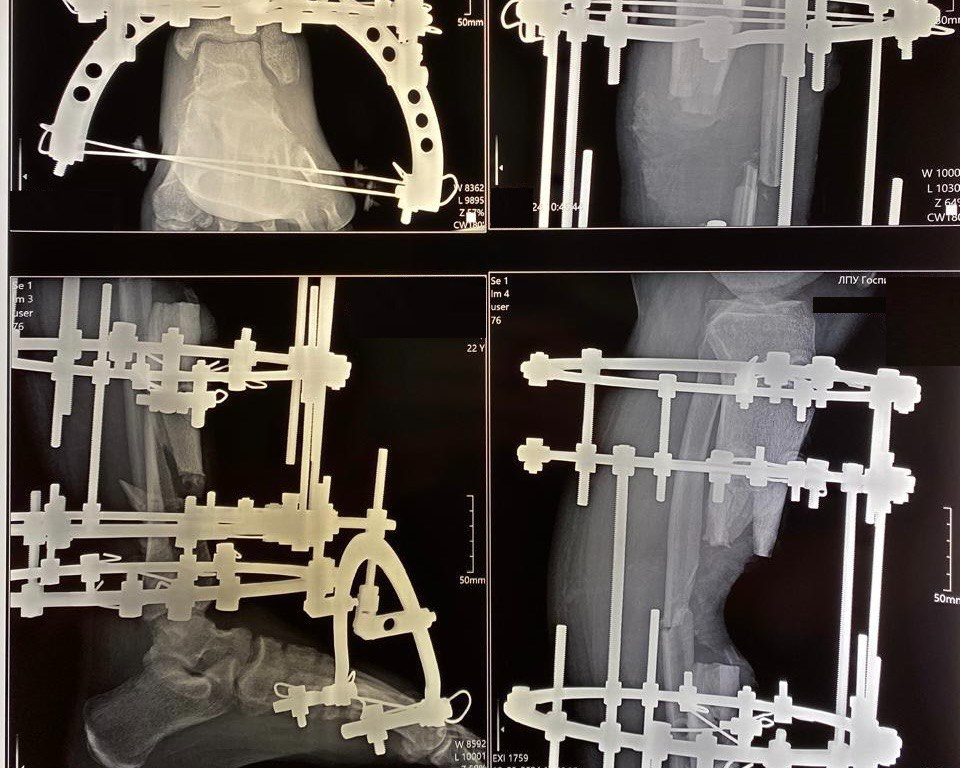

Хирурги Свердловского областного клинического психоневрологического госпиталя для ветеранов войн сохранили ногу участнику СВО, поступившему к ним после тяжёлого осколочного ранения голени от разрыва снаряда. В течение полутора лет медики миллиметр за миллиметром восстанавливали кость, чтобы избежать ампутации. Многоэтапное лечение, мастерство врачей и мужество пациента совершили чудо — мужчина снова может ходить на двух ногах.

Когда раненого бойца СВО эвакуировали с поля боя, его сломанная нога была зафиксирована примотанным автоматом. К моменту поступления пациента в Свердловский госпиталь для ветеранов войн ситуация стала критической: обширная инфекция и сложный перелом с дефектом кости создавали реальную угрозу жизни. Первоначально несколько врачебных комиссий рассматривали вариант ампутации, но мужчина отказался от этого пути и выбрал казавшееся практически невозможным поэтапное восстановление конечности.

Хирурги разработали план лечения, который длился полтора года. Основным инструментом стал аппарат Илизарова, с помощью которого врачи выполнили сложную фиксацию множественных осколочных переломов, боролись с хроническим остеомиелитом и инфекцией, постепенно, миллиметр за миллиметром, устранили костный дефект, восстановили длину и ось конечности и вернули ноге опорную функцию.